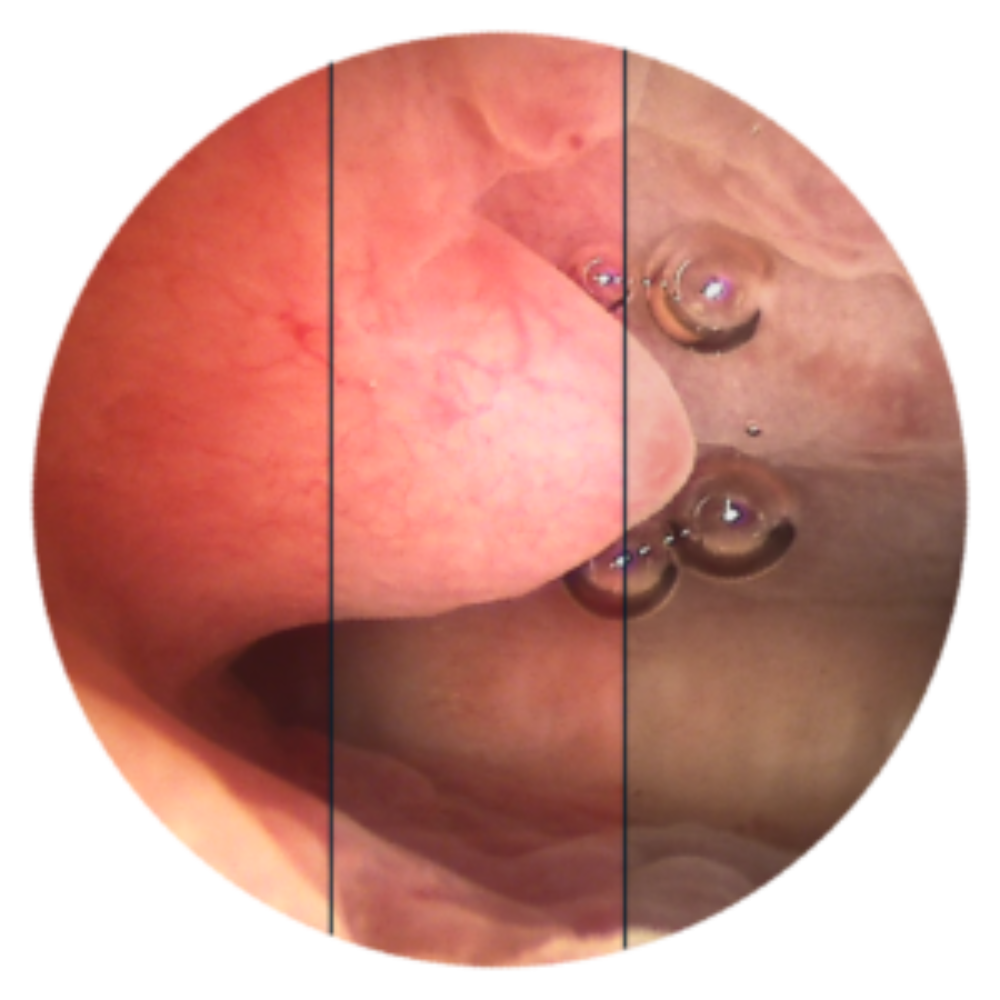

iCare ( L’hystéroscopie 2.0 )

La caméra d’endoscopie pensée pour les salles dédiées

L’association de la source de lumière et de la caméra dans un même boitier réduit considérablement l’encombrement, sans pour autant limiter les performances.

Le capteur CMOS HD d’une résolution de plus de 2 millions de pixels fournit une définition inégalée hors bloc et notre source de lumière LED procure une puissance garantissant une image lumineuse jusqu’à la périphérie, même avec un endoscope de petite taille.

Alliant design, simplicité et performances, iCare est la solution idéale pour les salles dédiées ! Retrouvez le confort de votre bloc opératoire pour une prise en charge optimale de vos patientes.

Notre toute dernière génération de lentilles, conçues pour tirer pleinement profit de la HD, procure des images riches, parfaitement résolues, même en périphérie. Cette hyper-résolution, couplée à une lumière répartie de manière véritablement homogène, est gage d’une très grande profondeur de champ.

Vous serez «net partout» ! Notre hystéroscope HD est bien entendu autoclavable. Sa conception sous forme de trois tubes distincts le rend résistant, durable mais aussi aisément réparable en cas d’accident.